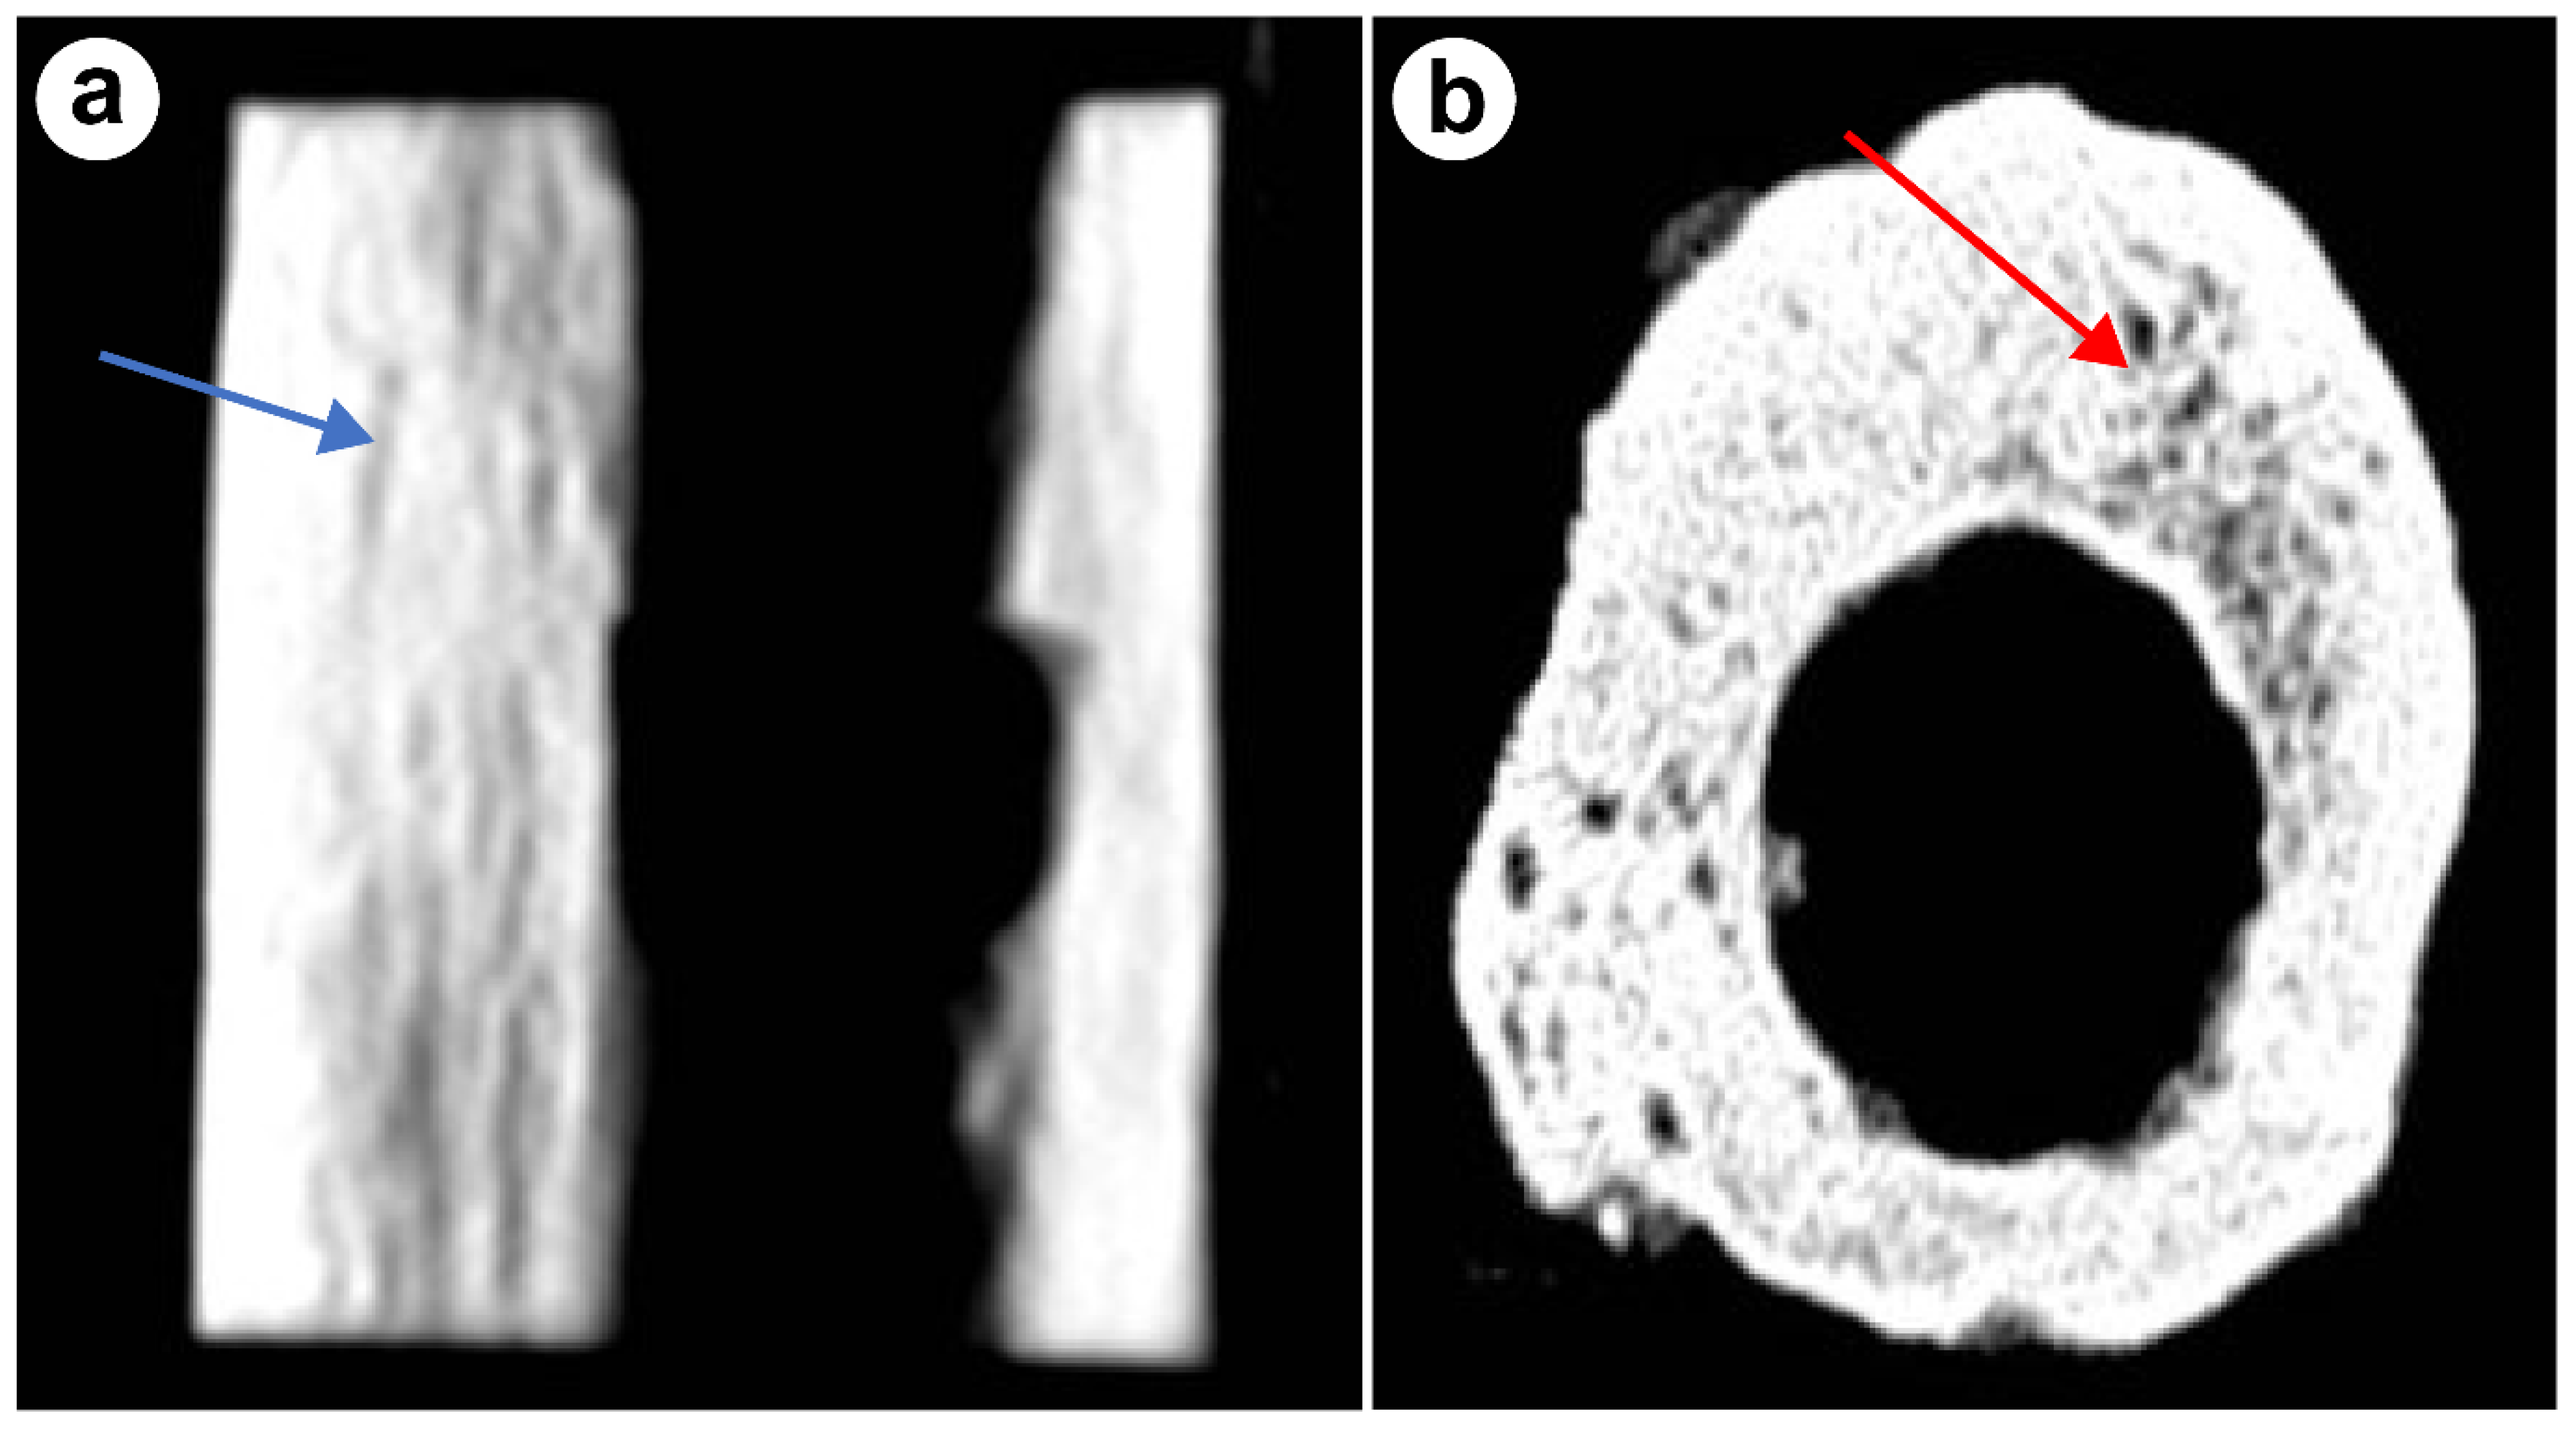

4.1.1. CT Scan Results

4.1.3. Electron Microscopy Results